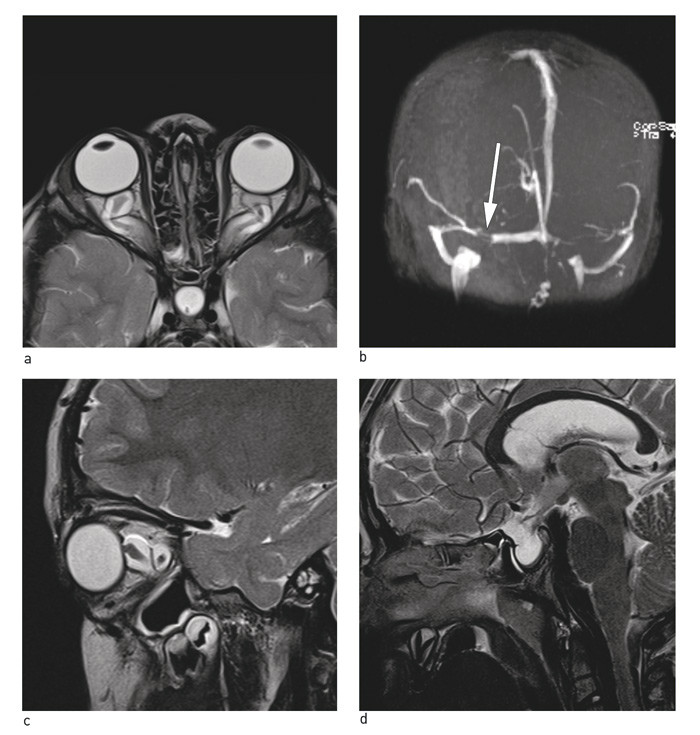

Hos de fleste med idiopatisk intrakranial hypertensjon vil fremstilling av venesinus ofte avdekke en viss grad av stenose i sinus transversus (fig 2a). Patofysiologisk mekanisme og årsaksforhold ved slike stenoser er ikke tilstrekkelig belyst. Asymmetrisk kaliber av sinus transversus mellom høyre og venstre side innebærer ofte ikke noe patologisk og er vanlig hos friske, mens enkelte hevder at manglende stenosering av sinusvenene kan være en grunn til å revurdere diagnosen idiopatisk intrakranial hypertensjon (1, 14).

Andre MR-funn som assosieres med tilstanden er såkalt tom sella (empty sella) og forandringer relatert til n. opticus og avflating av bakre øyepol (fig 2b – d). Ingen MR-funn har kombinert høy sensitivitet og spesifisitet, og få har studert prediktiv verdi av kombinasjoner av radiologifunn (14). I en studie med barn med idiopatisk intrakranial hypertensjon fant man at kombinasjonen av tre eller flere MR-funn (sinusvenestenose ikke inkludert) hadde en sensitivitet på 45 % og en spesifisitet på 95 % (14). Figur 2a – d viser eksempler på typiske MR-funn assosiert med idiopatisk intrakranial hypertensjon. Der det er kontraindikasjon mot MR-undersøkelse er CT-undersøkelse med kontrast og CT-venografi et godt alternativ.